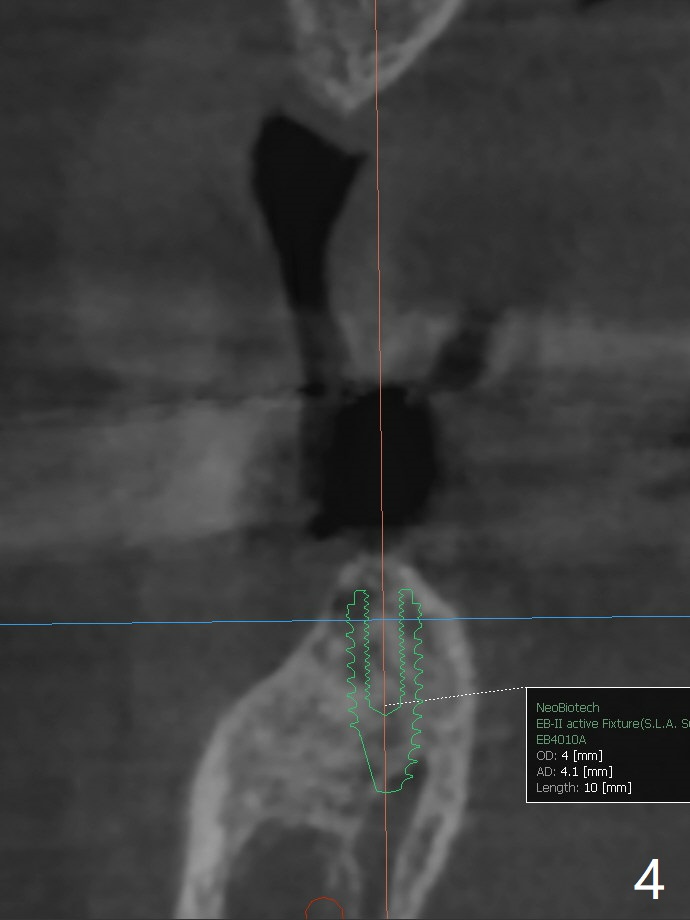

A 64-year-old woman with partial edentulism requests an implant for #30 after #29 crown temp bond cementation (Fig.1). The buccal, crestal and lingual cortex is equally thin (no deviation). The medulla is porous. The average bone density is 600 units. Ask the patient about osteoporosis treatment. A 4.5x10 mm implant with deep placement is going to have 2 mm bone buccal and lingual. Underprep is necessary (the last drill 3.5x10 mm). Due to metal scattering from amalgam from #28,29,31, a larger field view of CT is taken (Fig.2). Although the cancellous bone looks porous (Fig.3), the average bone density is 1000 units. The 2nd analysis shows that the ridge is narrower, allowing safe placement of a 4 mm implant (Fig.4,5). In spite of keratinized gingiva in the edentulous area, incision will be made to make sure the ridge top is being flattened by bone trimmer. If it is insufficient, use rotary instruments.